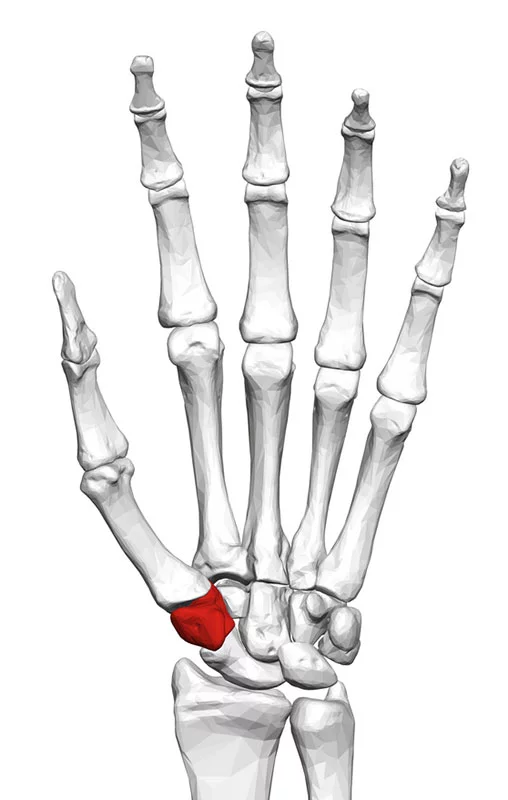

The traditional surgery to cure advanced carpometacarpal (CMC) arthritis involves removing the trapezium bone, depicted in red in the wrist bones of a left hand, with a bundle of tendon. The Touch CMC 1 prosthesis instead embeds in the bone, making for a less pain, better function, and a much faster recovery. Image via Wikimedia Commons via BodyParts3D, The Database Center for Life Science.

The traditional surgery to cure advanced carpometacarpal arthritis involves removing the trapezium bone, depicted in red, with a bundle of tendon. The Touch CMC 1 prosthesis instead embeds in the bone, making for a less pain, better function and a much faster recovery. Image via Wikimedia Commons via BodyParts3D, The Database Center for Life Science.

The trapezium is one of the eight carpal bones that help the wrist function. The trapezium doesn’t look like much. Averaging around a half inch in diameter and just under an inch long, it evokes an oversized molar that got lost on the way to the mouth.

The trapezium anchors the thumbs, and when it malfunctions, it can cause severe arthritic pain and associated grip weakness.